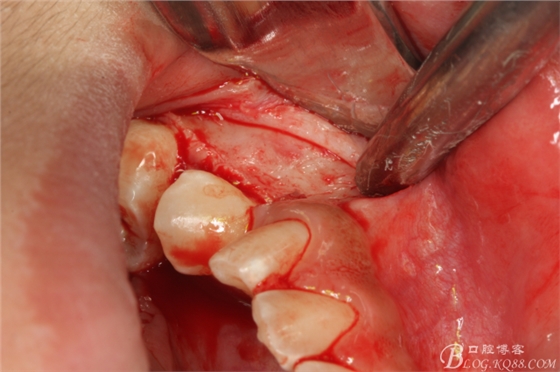

圖4. 翻瓣 (三角形瓣)